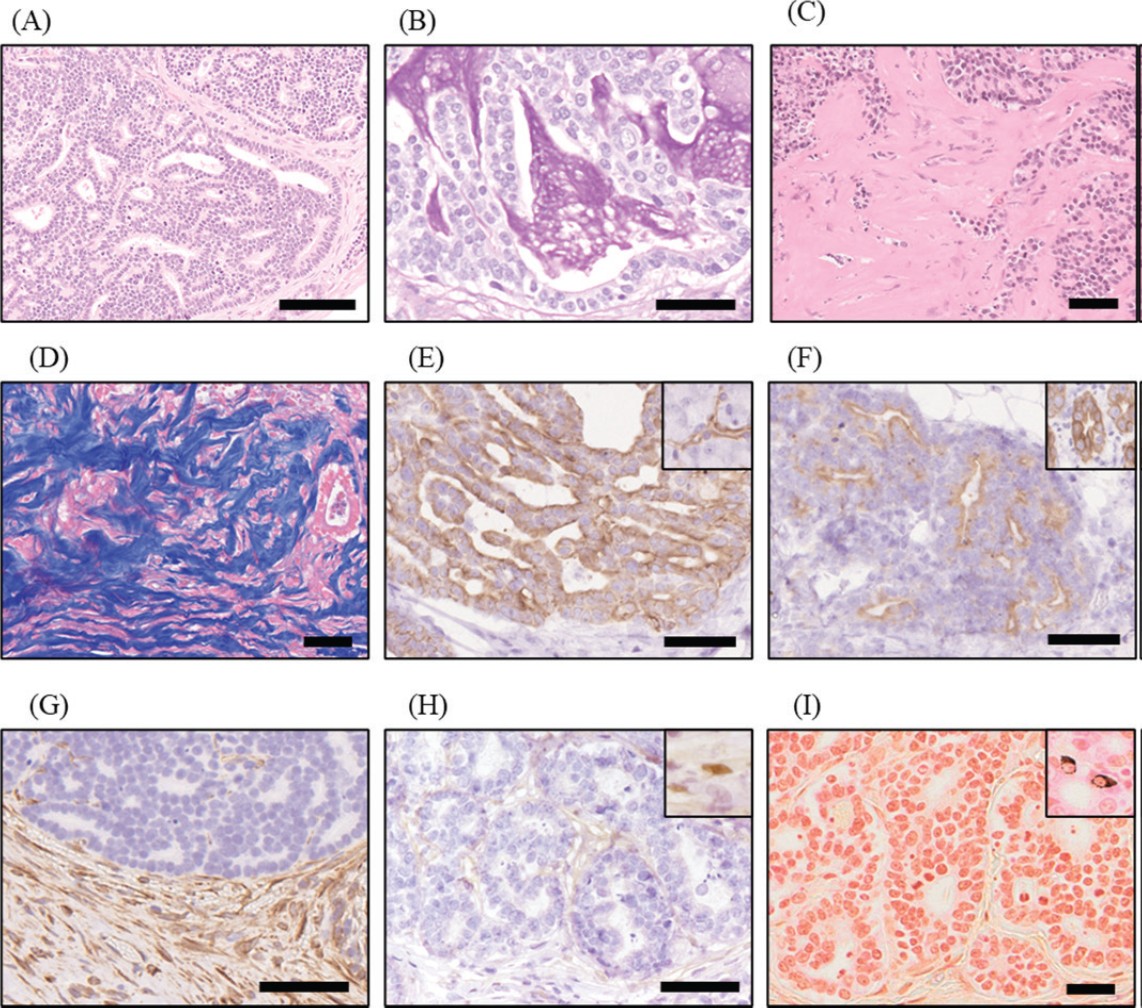

组织病理学检查显示,胰腺出现肿瘤细胞的浸润性增殖,形成导管结构和片状增殖模式,肿瘤组织中心出现坏死和部分黏液分泌,提示为原发性胰腺肿瘤(下图A-B)。在大网膜、小网膜、肠系膜和腹膜壁中,观察到具有类似特征的肿瘤细胞浸润性增殖,少量炎症细胞存在以及显著的纤维化(下图C-D)。腹壁、膈肌、膀胱浆膜和肺部观察到转移性病变。肿瘤细胞对细胞角蛋白AE1/AE3、细胞角蛋白7和细胞角蛋白20呈阳性反应,对波形蛋白呈阴性反应,表明肿瘤组织分化为胰腺外分泌细胞,特别是胰腺导管上皮细胞(下图E–G)。尽管这些发现与外分泌性胰腺腺癌的诊断标准一致,但细胞角蛋白7和20的免疫阳性率约为20%或更低。肿瘤细胞对WT1抗体呈阴性反应,Grimelius染色亦呈阴性,排除了间皮瘤和神经内分泌肿瘤(下图H-I)。

↑ 组织病理学发现。(A)肿瘤组织增殖,形成导管结构和片状模式。(B)肿瘤导管结构内腔中的黏液对过碘酸雪夫氏(PAS)反应呈阳性。(C)在腹膜肿瘤组织的基质中观察到严重的纤维化。(D)肿瘤组织基质中的纤维化区域通过Azan染色呈深蓝色。(E)肿瘤细胞对细胞角蛋白7呈阳性反应。该病例中胰腺的导管细胞(插图)对同一种抗体也呈阳性反应。(F)肿瘤细胞对细胞角蛋白20呈阳性反应。该病例中的肠上皮细胞(插图)对同一种抗体呈阳性反应。(G)肿瘤细胞对波形蛋白抗体呈阴性反应,而周围的基质细胞,包括成纤维细胞,呈阳性反应。(H)肿瘤细胞对WT1抗体呈阴性反应。该病例中的间皮细胞(插图)对同一种抗体呈阳性反应。(I)肿瘤细胞对Grimelius染色呈阴性反应。分布在肠上皮细胞中的神经内分泌细胞(插图)对Grimelius染色呈阳性反应。